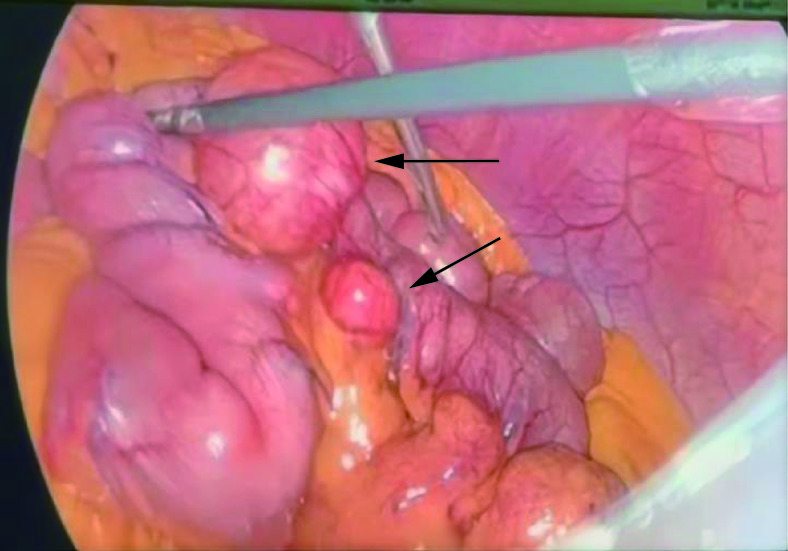

2.1 手术所见

全麻下行腹腔镜小肠部分切除术。术中腹腔镜可见空肠近段(距屈氏韧带约10~50 cm)肠管多发大小不等的憩室(图4),共计约17枚,憩室直径1~3 cm,部分肠管粘连。术中可见部分憩室充血水肿,周围可见渗出,个别憩室与肠系膜上静脉相通,另术中部分肠系膜上静脉内可见血栓。